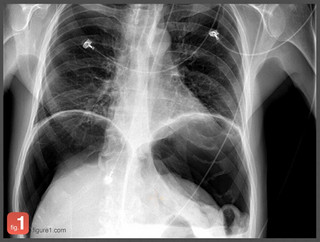

Μέσα σε τουλάχιστον 24 μήνες, το λεγόμενο «Instagram για γιατρούς» έχει δεχτεί εκατοντάδες χιλιάδες ενεργούς χρήστες που έχουν ανεβάσει πάνω από δυο εκατομμύρια τέτοιες φωτογραφίες που βλέπετε-οι περισσότερες είναι συγκλονιστικές που μόνο γιατροί μπορούν να δουν χωρίς να σοκάρονται (έχουμε επιλέξει για το θέμα αυτό τις πιο ανώδυνες)-, από σπάνιες ή περίεργες παθήσεις.

Η εφαρμογή, που ονομάζεται Figure 1, επιτρέπει σε γιατρούς από όλο τον κόσμο να ανεβάζουν ανώνυμα φωτογραφίες από τις πιο περίπλοκες ιατρικές υποθέσεις τους σε μια κοινή φωτογραφική πλατφόρμα με στόχο την ανταλλαγή πληροφοριών και συμβουλών.